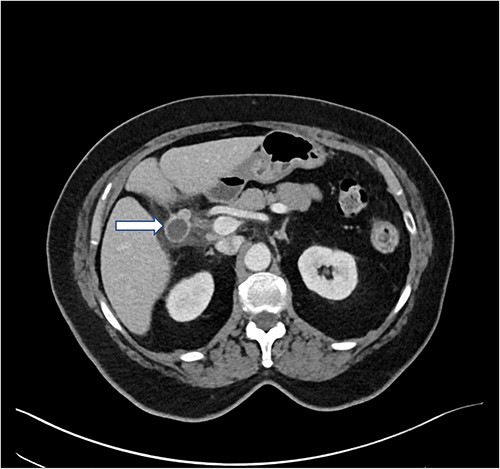

This is the case of a 70-year-old female with a history of hypothyroidism, hiatal hernia, irritable bowel syndrome and obstructive sleep apnea, with a surgical history of open small bowel resection due to endometriosis 46 years prior, total abdominal hysterectomy 40 years prior and laparoscopic cholecystectomy 4 years prior at an outside institution. She presented with colicky right upper quadrant abdominal pain similar to previous gallbladder attack. She was hemodynamically stable and afebrile. Labs were notable for leukocytosis, with a count of 14.9 k/ml and neutrophilia of 87%. Hepatic enzymes and bilirubin levels were unremarkable. A computed tomography (CT) scan of abdomen/pelvis demonstrated a 2.2 × 1.9 cm peripherally enhancing tubular/cystic structure in the gallbladder fossa, containing air and fluid, contiguous with postsurgical clips (Fig. 1). Surrounding fluid and fatty infiltration were observed. Findings raised the possibility of a dilated CDR with superimposed infection. No intrahepatic ductal dilatation was observed. The patient was discharged on oral Augmentin 875–125 mg bid and scheduled for interval surgical intervention, 10 days later.

Preoperative CT abdomen/pelvis with IV contrast. In the gallbladder fossa, a 2.2 × 1.9 cm peripherally enhancing tubular/cystic structure is observed (arrow), dilated with air and fluid and contiguous with postsurgical clips, status post cholecystectomy. Moderate surrounding fluid and fatty infiltration are observed. The findings raised the possibility of a dilated remnant cystic duct with superinfection, abscess or less likely, biloma. Neither intrahepatic duct nor common bile duct dilatation was observed. There was concern for probable adjacent secondary duodenitis. Minimal pelvic ascites was observed.